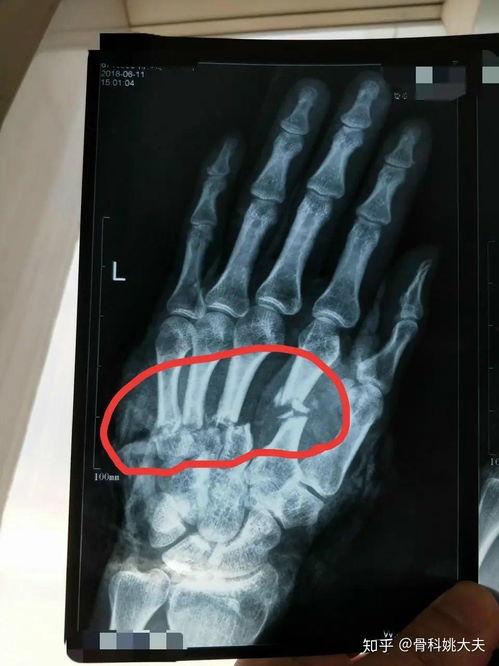

手骨骨折图片,影像学诊断与治疗策略 最近是不是不小心摔了一跤,手骨骨折了?别担心,今天就来给你详细介绍一下手骨骨折的情况,让你对它有个全面的认识。咱们就从那些让人看了都心疼的手骨骨折图片开始吧!一、手骨骨折的常见类型首先,你得知道手骨骨... admin 爆料求搞 2026-02-22 9 0